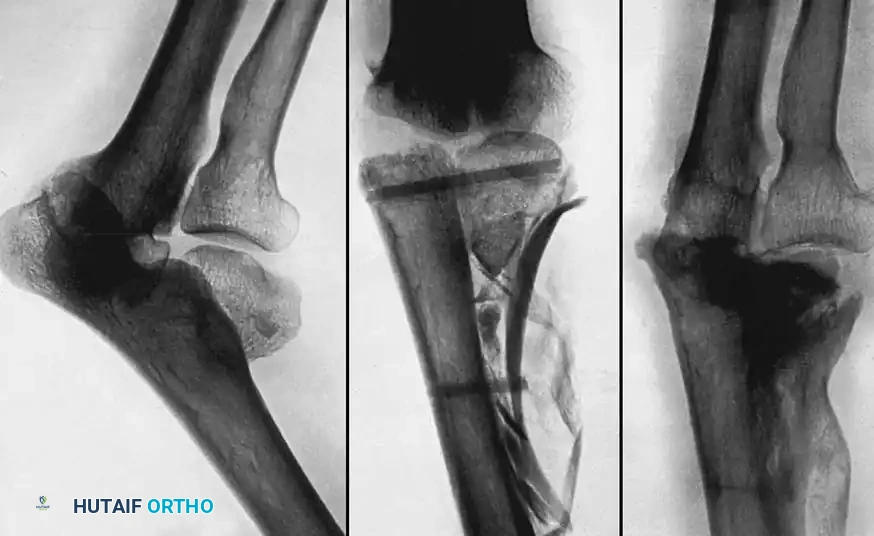

Medial Malleolus

A fracture of the medial malleolus occasionally fails to unite, especially after nonoperative (closed) treatment where periosteum or the deltoid ligament may interpose between the fracture fragments.

Surgery may be indicated for the few nonunions in which other serious complications of the fracture, such as advanced traumatic arthritis, are not seen on radiographs, and ideally if the injury is less than 2 years old. The standard surgical technique usually includes excision of the fibrous nonunion, application of autogenous bone grafts, and rigid internal fixation of the malleolar fragment.

Technique 56-8: Bone Graft of Tibial Nonunion (Banks Technique)

- Exposure: Expose the nonunion through a medial longitudinal incision 10 cm long.

- Preparation: Freshen the fracture surfaces by removing sclerotic bone to create a wedge-shaped defect with its apex directed toward the articular surface of the ankle. Ensure damage to the articular cartilage is minimal.

- Reduction and Fixation: Restore the fragments to their normal anatomic position. Hold them gently with a large pointed reduction forceps (towel clip) and fix them with a 4.5 mm cortical or 4.0 mm cancellous lag screw.

- Window Creation: Make a cortical window in the tibial metaphysis at the proximal end of the surgical wound by removing a square piece of bone with its edges undercut.

- Grafting: Harvest cancellous bone through this window using a curette. Pack this autologous cancellous bone tightly into the wedge-shaped defect at the nonunion site.

- Closure: Replace the square piece of cortex over the metaphyseal window and close the wound in layers.

Fig. 56-19 Technique for grafting nonunion of medial malleolus (Banks).

Postoperative Protocol: The aftertreatment is identical to that of the sliding graft technique.